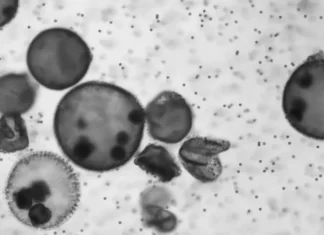

Algae – Based Microrobots Fight Cancer

Residing microrobots crafted from algae have been weaponized to help combat tumors with the aid of improving the effectiveness of cancer treatment plans.

for the duration of most cancers' development, strong tumors usually expand regions with limited get entry to nutrients and oxygen. The odd shape of blood vessels and a high fee of...